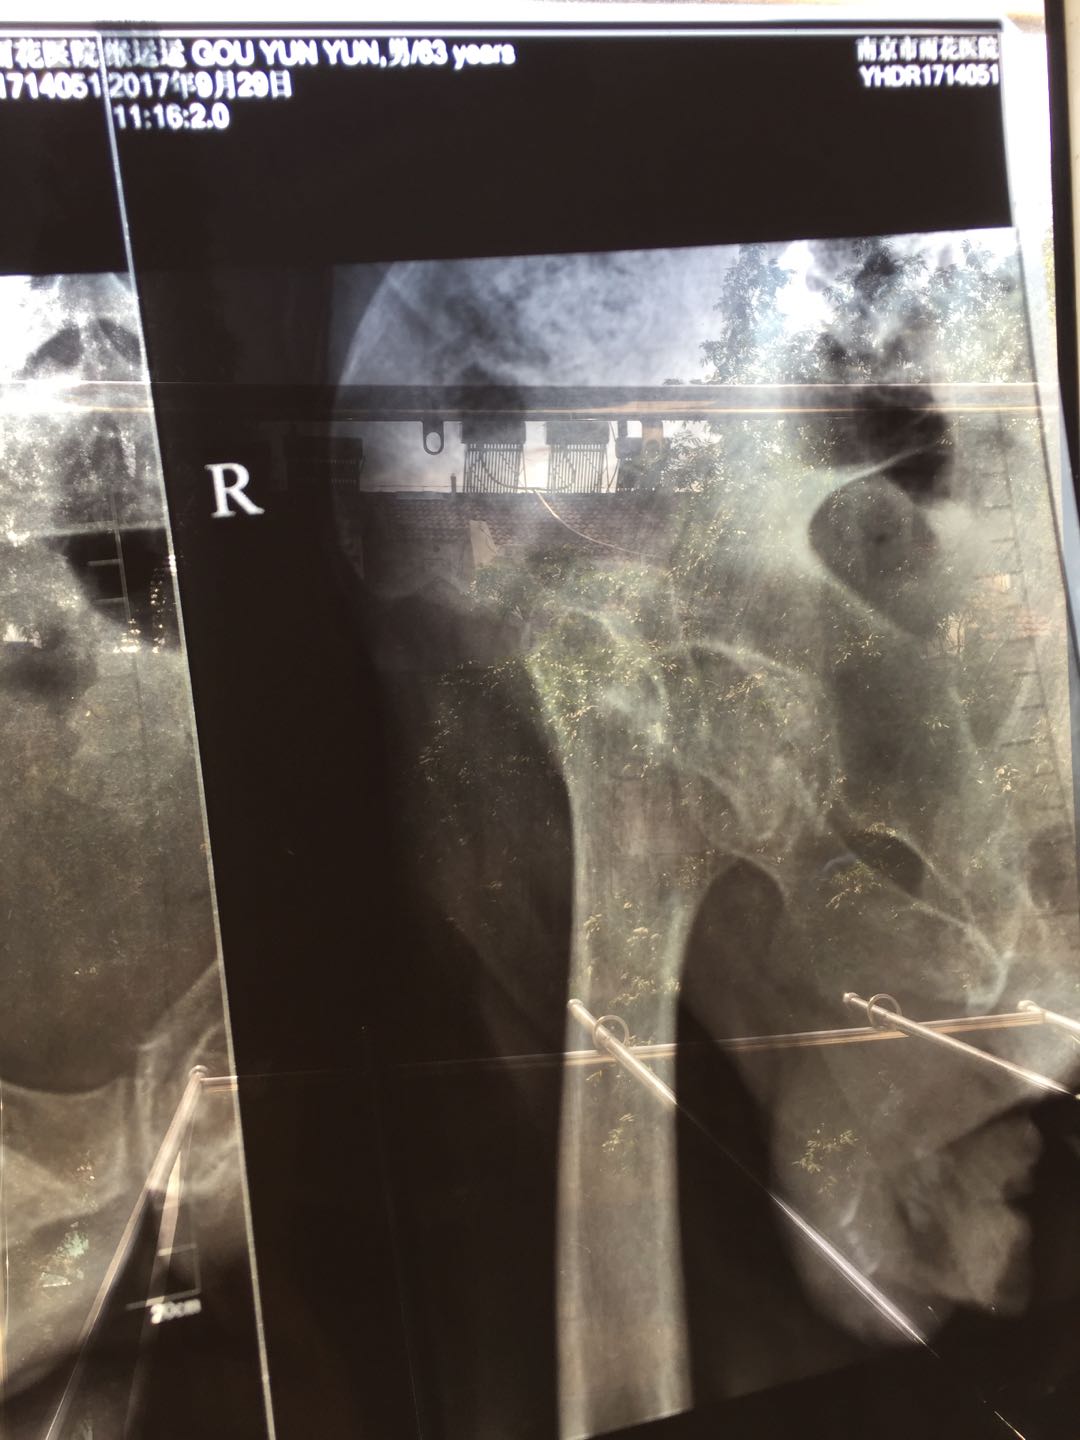

#1962747 - 2017-12-25 06:23:30 求做了股骨頭置換手術後是否可以獨立行走(柱拐棍也算獨立行走),父母大事,懇請各位大大出手,謝謝

3.起卦者:本人,基本資料:GouYunyun 陝西西安臨潼區人,生於陰曆1953年10月14日,身高176,駝背,2005年患類風濕,身體處於半殘疾狀態,2017年3月在家跌倒,臥床2個月後,需雙拐方可行動(以前可以緩慢行走),2017年7月又摔一次,9月29日發現股骨錯位,需要更換股骨,現在正在猶豫是否更換。主要擔心更換後是否能脫離雙拐,獨立行走。

8.對於現況的描述:股骨骨折錯位,醫院建議更換股骨,現在正在猶豫是否更換。主要擔心更換後是否能脫離雙拐,獨立行走。

您說的對,目前我也擔心後面筋骨拉不開,現在股骨明顯錯位約5CM,而且時間已經過了大半年。而我父親不是那種意志非常堅強的人!

錯位圖片.jpg